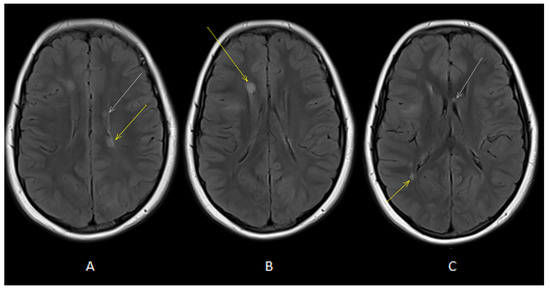

Figure 2.

Axial T2-FLAIR images (A,B) showed oval-shaped lesions in deep periventricular white matter of both cerebral hemispheres (white and yellow arrows). Axial T2-FLAIR image (C) showed oval-shaped lesions in deep periventricular white matter (yellow arrow) and in the corpus callosum (white arrow).